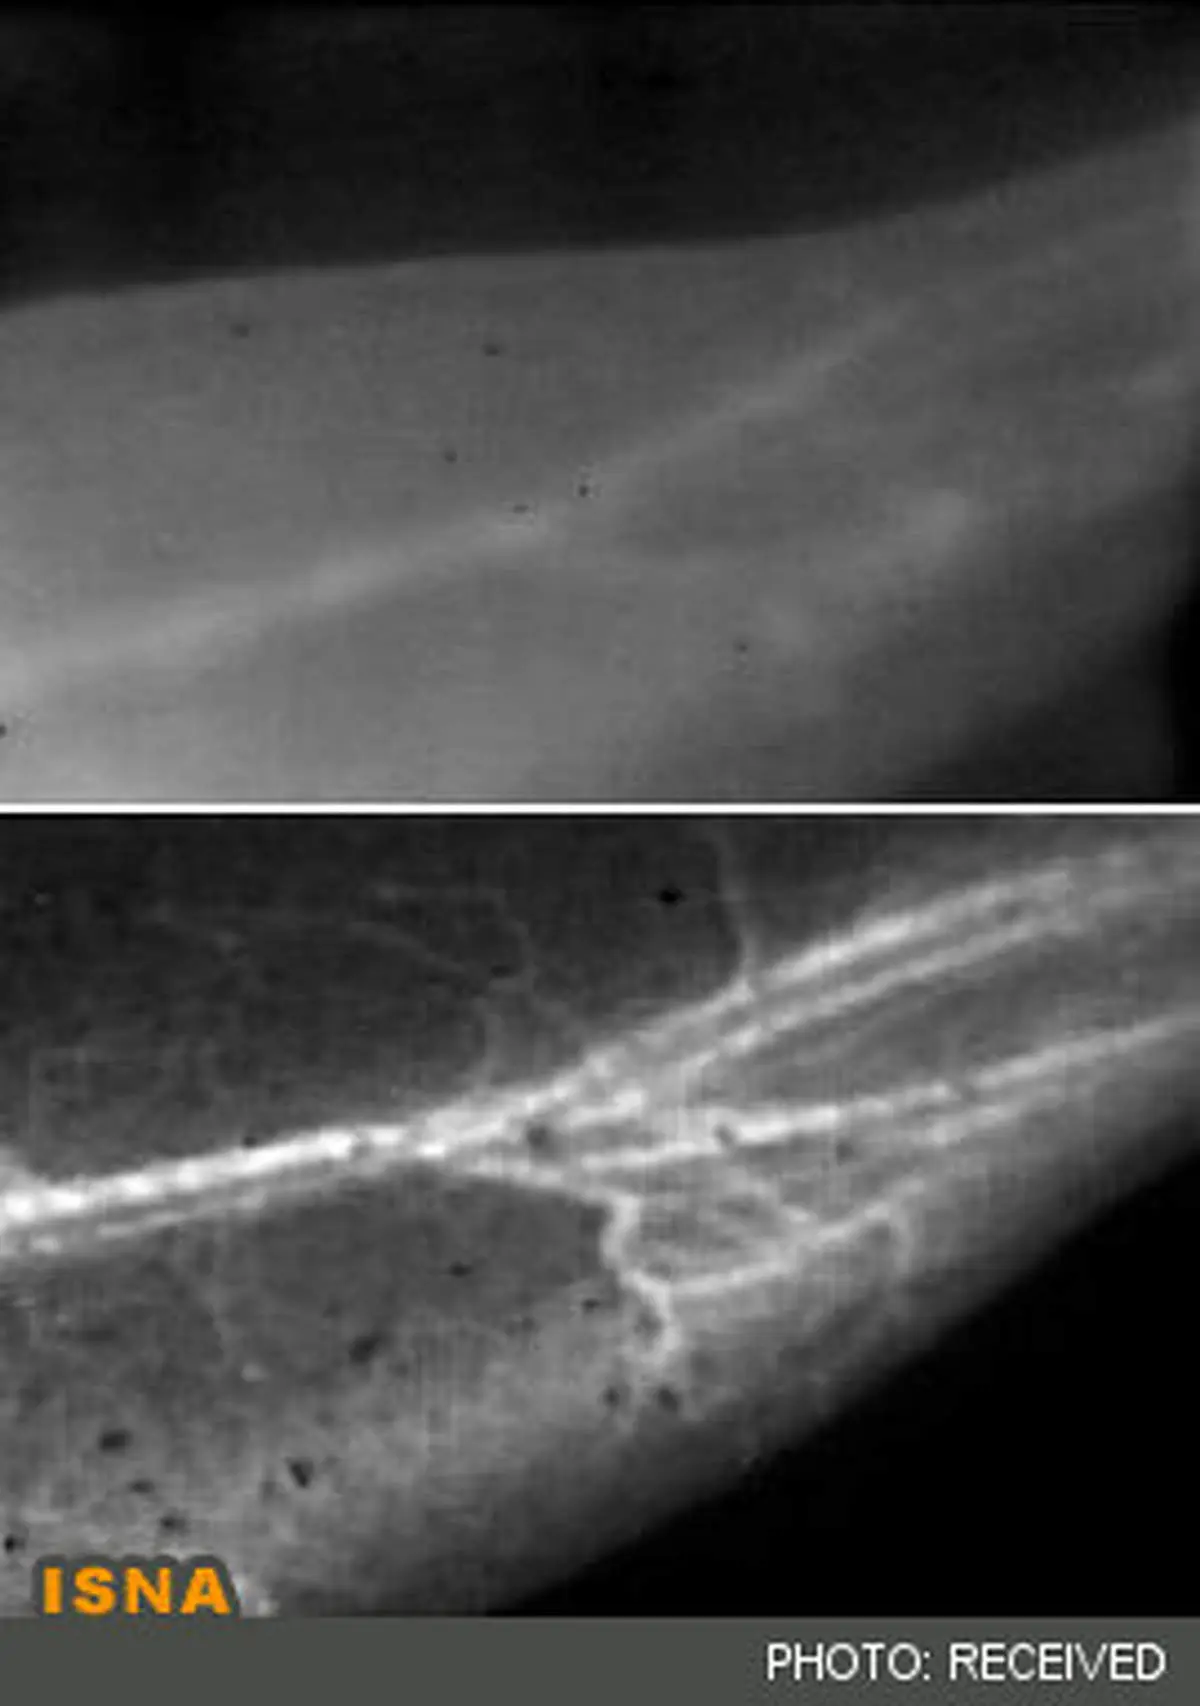

دانشمندان دانشگاه استفورد روشی در تصویربرداری فلورسانس ابداع کردهاند که دیدن رگهای خونی حیوانات را با وضوح بیسابقهای میسر میکند.

به گزارش سرویس فناوری ایسنا، وضوح تصاویر در این روش به حدی است که مقایسه آن با تصاویر گرفته شده با روشهای مرسوم به منزله پاک کردن بخار از روی شیشه عینک به نظر میرسد.

این روش که تصویربرداری نزدیک به مادون قرمز یا همان NIR-II نام گرفته است، در مرحله اول شامل تزریق نانولولههای کربنی محلول در آب در جریان خون موجود زنده است. این محققان سپس یک باریکه نور لیزر، نوری در محدوده نزدیک به مادون قرمز با طولموجی در حدود هشت دهم میکرون را به موجود زنده که در این مورد یک موش است، میتابانند.

اصل بازتابندگی ذاتی نانولولهها در طولموجهایی بلندتر از روشهای مرسوم تصویربرداری نکته اساسی در دستیابی به این تصاویری با وضوح فوقالعاده حتی در رگهای ریز خون است. نور با طولموج بلندتر کمتر پراش شده و بنابراین تصاویری واضحتر را از رگها ایجاد میکند.

از مزایای دیگر آشکارسازی نور با چنین طولموج بلندی این است که آشکارساز، مزاحمتهای پیشزمینه را کمتر ثبت میکند، زیرا که بدن در این طولموج از خود خاصیت خودبازتابی نشان نمیدهد. علاوه بر ایجاد کوچکترین جزئیات در تصویر، این روش سرعت تصویربرداری بالایی داشته و محققان را قادر میکند تا جریان خون را بطور آنی ثبت کنند.